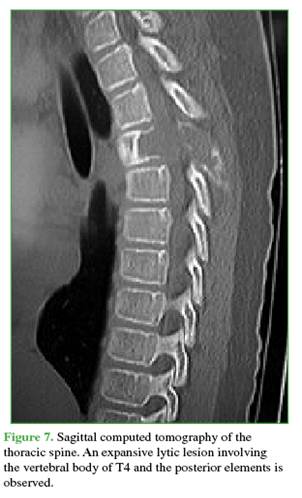

The lesion involved zones 3-6 and levels III and IV of the Weinstein-Boriani-Biagini classification.11 Complementary imaging studies showed multiple septated cysts with fluid-fluid levels. A simple bone cyst with expansile and compressive features was ruled out, as was vertebral hemangioma (Figures 7 and 8). This case was also interpreted as an Enneking grade 3 ABC.13